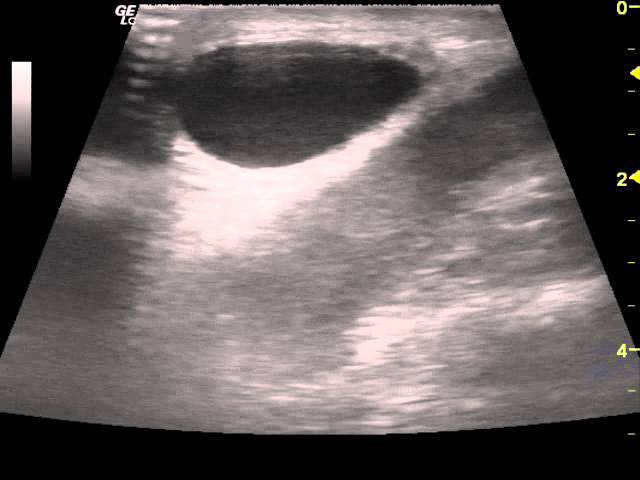

Пример патологии на фото:

- Кисты яичек, придатков – жидкостные образования. Кисты могут располагаться на любом органе, иметь разные размеры. При УЗИ определяются как объемные округлые образования с четкими контурами, содержащие жидкость внутри, иногда имеются перегородки. Кисты могут сдавливать придатки, приводя к бесплодию.

- Водянка яичка – гидроцеле. Определяется при выявлении увеличенных размеров мошонки, анэхогенности, скоплении большого объема жидкости.